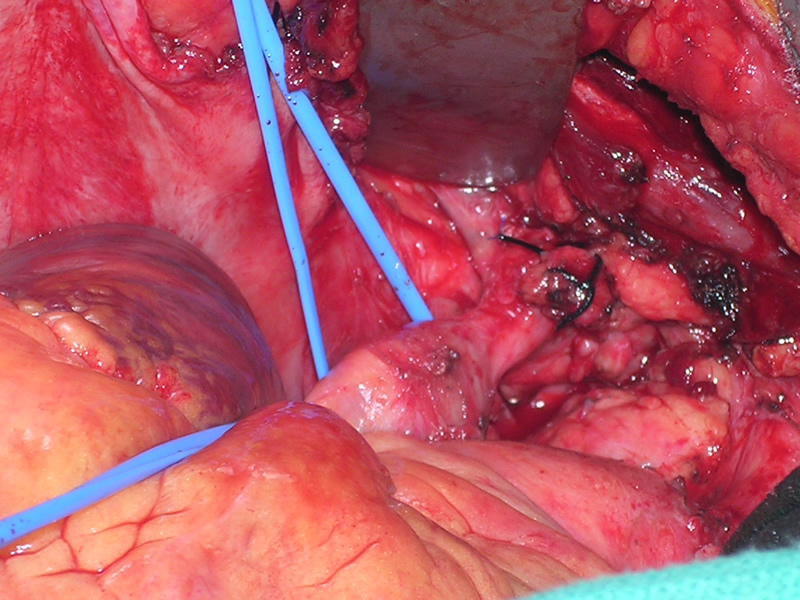

The patient was taken to the operating room where a standard median sternotomy was performed. Inspection revealed a left brachiocephalic vein that was completely obliterated and non-functioning. The SVC was normal at its junction with the right atrium, but at approximately mid level it was noted to be scarred and atretic to the level of the right internal jugular and right subclavian veins (Figures 2 and 3). Simultaneously the left saphenous vein, from inguinal canal to the ankle, was harvested endoscopically (Figure 4). Once harvested the vein was incised and opened longitudinally along its entire length. Using a standard 2-stage venous cannulae, a spiral vein graft was constructed using running 7-0 prolene suture, exchanging suture with each completed turn (Figures 5 and 6). The vein graft was left on the end of the cannulae and using a parachute technique an end-to-end anastomosis was first created in the distal SVC at the confluence of the right internal jugular and subclavian veins. The proximal anastomosis was constructed below the level of the obstruction at the entry area of the azygous vein. Following de-airing, inspection revealed the vein graft to be widely patent with no thrill or kinking (Figure 7). The patient was discharged home with coumadin with goal INR of 2.0 for 6 months. At six month follow-up, the patient reports significant improvement in her symptoms.

| Figure 2 | Figure 3 | Figure 4 |